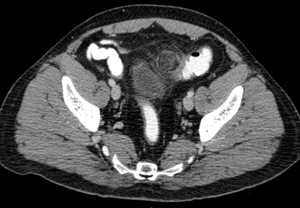

УЗИ брюшной полости проводится для уточнения локализации и размера аппендикулярного абсцесса, выявления скопления жидкости в области воспаления. При обзорной рентгенографии органов брюшной полости определяется гомогенное затемнение в подвздошной области справа и небольшое смещение петель кишечника в сторону срединной линии; в зоне аппендикулярного абсцесса выявляется уровень жидкости и скопление газов в кишечнике (пневматоз). Аппендикулярный абсцесс необходимо дифференцировать с перекрутом кисты яичника, разлитым гнойным перитонитом, опухолью слепой кишки.

- УЗИ. При проведении УЗИ брюшной полости у детей удается выявить расширенный (более 6 см в диаметре) червеобразный отросток, наличие свободной жидкости в правой подвздошной ямке; при перфорации аппендикса обнаруживается периаппендикулярная флегмона.

- Другие инструментальные методы. При неоднозначности в трактовке клинических и физикальных данных ребенку может потребоваться выполнение рентгенографии или КТ брюшной полости. У младших детей с целью выявления защитного мышечного напряжения применяется электромиография передней брюшной стенки.

- УЗИ. Позволяет выявить уплотненные лимфоузлы. Обязательно проводится УЗИ всех органов брюшной полости, чтобы исключить болезни с похожими проявлениями - панкреатит, аппендицит и другие.

- Рентген брюшной полости. Проводится для исключения доброкачественных или злокачественных опухолей в области кишечника.

- МРТ. Это очень точный диагностический метод. С его помощью можно узнать точное расположение воспаленных лимфоузлов, их размер. МРТ позволяет обнаружить любые нарушения в работе органов ЖКТ.